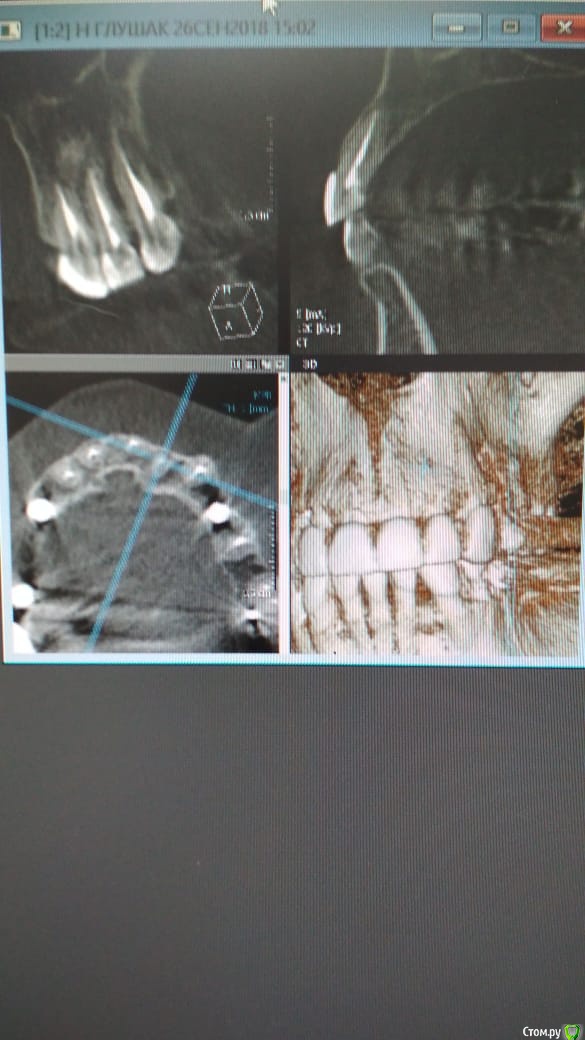

Alexandr_doc Опубликовано 21 сентября, 2018 Поделиться Опубликовано 21 сентября, 2018 Доброго всем времени! Пациентку протезировал доктор, которого уволили по ряду причин, обратилась ко мне на этапе после протезирования с жалобами на болезненность в области фронтальной группы зубов 1.2, 1.1, 2.1, 2.2, 2.3 при дотрагивании языком или пальцем. Перкуссия положительная как в вертикальном так и горизонтальном направлении. Установлены одиночные керамические коронки на каркасе из диоксида циркона. Отек, покраснение в области переходной складки отсутствует, также отсутствует болезненность при пальпации. Подвижность 1 степени. Прилагаю фотографии на этапе обращения. Ранее, на этапе протезирования было принято решение о депульпировании фронтальной группы тк присутствовала пульпитная симптоматика, после чего состояние улучшилось и остается стабильным по сей день. Предположил несколько причин оставшейся симптоматики: 1) несостоятельно проведенное эндо лечение - вариант отмел тк по прицельным снимкам и кт отсутсвуют очаги воспалительных процессов 2) некорректно изготовленные искуственные коронки ( глубокая поддесневая препаровка и агрессивный контур коронки ) 3) - окклюзионная перегрузка. Совместно с пацинеткой принято решение о снятии коронок во фронтальном отделе, была предупреждена о том, что возможно не получить хорошей динамики. С переменным успехом картина после нескольких корректировок временных коронок остается преждней. Болезненность на прежднем уровне, плюс по ходу наблюдения пришлось снять мост с опорой на уровне имплантатов, тк имели место быть воспалительные процессы в проекции имплантата 1.5. С удовольствием отвечу на все вопросы и приму любую критику. Ссылка на комментарий

Alexandr_doc Опубликовано 26 сентября, 2018 Автор Поделиться Опубликовано 26 сентября, 2018 Прошу извинить за задержку. Прикладываю срезы со свежего КТ. Поступили предложения о хир удлинении, на мой взгляд это в данной ситуации очень рискованно. Ссылка на комментарий